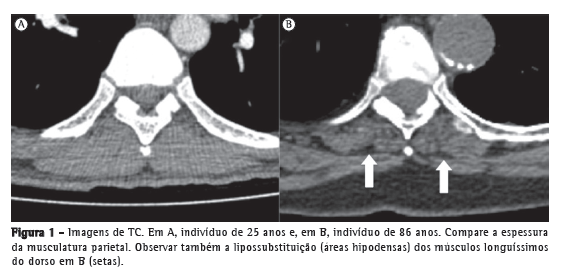

Alterações radiológicas relacionadas ao envelhecimento da caixa torácicaUm dos achados radiológicos mais comuns na parede torácica é a redução da espessura dos músculos parietais, que é bem demonstrada por TC, especialmente quando comparada com aquela de indivíduos mais jovens (Figura 1). Essa redução é uma das principais causas do aumento da transparência pulmonar em estudos radiográficos de tórax em idosos. Apesar de não haver estudos definindo a idade inicial para o encontro desse achado, sabe-se que isso decorre da perda de massa muscular associada ao processo fisiológico de envelhecimento, sendo mais evidente quanto maior for a idade do indivíduo.(4-10) Entretanto, não existem ainda critérios objetivos que permitam diagnosticar esse achado pelos métodos de imagem. Outro achado de ocorrência comum é a presença de calcificações da cartilagem costal, que se apresentam como pequenas ilhas de matéria óssea compacta e que podem ter aparência nodular, sendo confundidas, em alguns casos, com nódulos pulmonares solitários.(3)